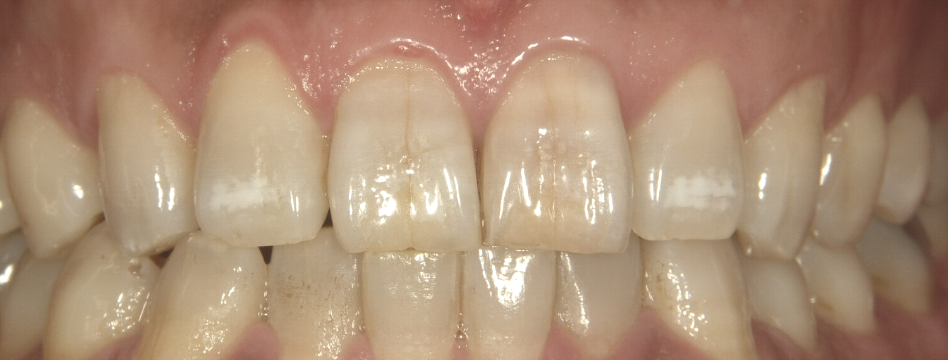

症例2

治療方法 変色した歯:セラミッククラウン法

詰め物跡のヒビ:ダイレクトボンディング

ホワイトニング

治療期間 2ヶ月

治療費用 ファイバーコア+セラミッククラウン 1歯 ¥181,500(税込)

ダイレクトボンディング 1歯 ¥33,000(税込)

治療の副作用.リスク 詰め物は経年劣化で変色する

歯を削る必要がある

セラミッククラウン法+ダイレクトボンディング+ホワイトニング

神経を取った歯の根もとにヒビが入っていることと変色がお悩みでした。神経を取ってから10年ほど経過すると変色や歯の劣化が進み、見た目だけでなく歯の強度も損なわれます。

このような場合は、歯の内部に土台を入れて補強した後にセラミッククラウンで被せることで強度と審美性が得られます。